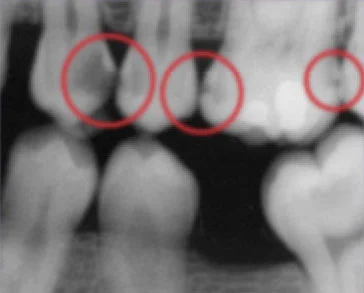

This bitewing shows several areas of decay between (and within) teeth.